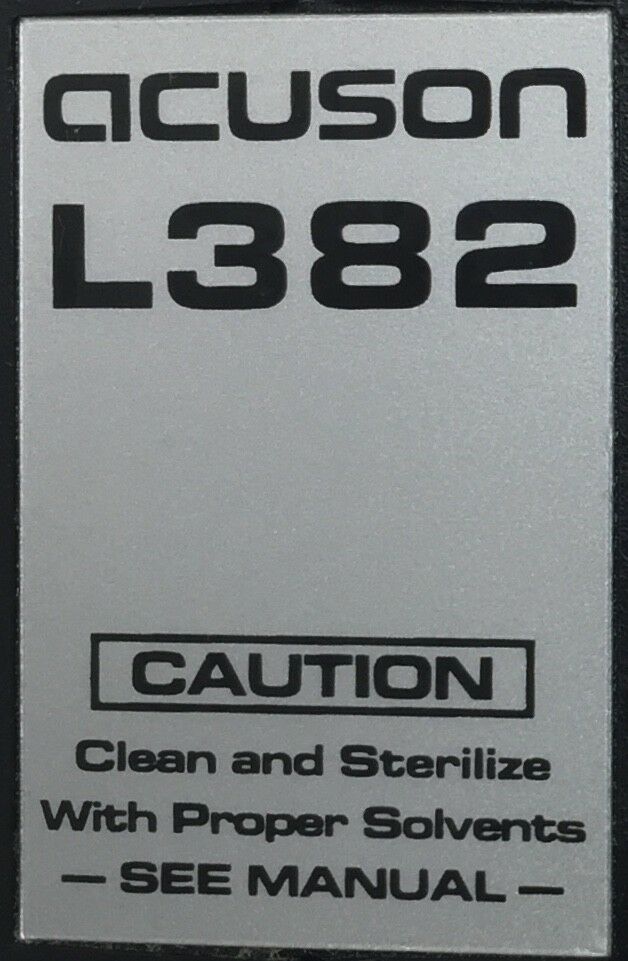

Acuson L382 3.5 MHz Linear Array Ultrasound Transducer Probe.USED TESTED

The Acuson L382 3.5 MHz Linear Array Ultrasound Transducer Probe is a used, tested, and fully functional device designed for high-resolution imaging. Ideal for vascular, musculoskeletal, and superficial tissue assessments, the 3.5 MHz frequency provides excellent detail for imaging of smaller structures. This transducer is compatible with Acuson ultrasound systems and is designed to deliver clear, reliable results for diagnostic applications. Despite being a used unit, it has been thoroughly tested to ensure it meets performance standards. It's a cost-effective solution for healthcare professionals seeking a quality ultrasound probe for detailed imaging.